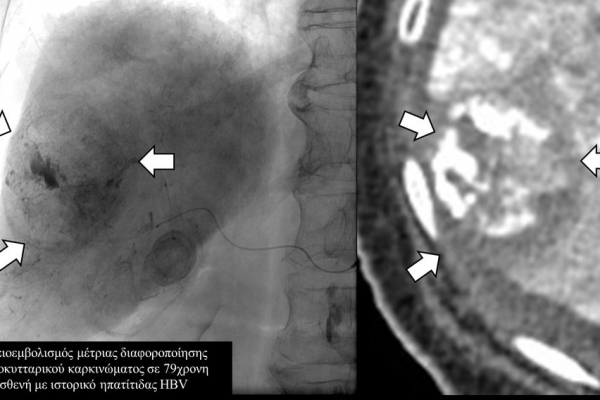

Ο χημειοεμβολισμός έχει καθιερωθεί σαν θεραπεία εκλογής στο ενδιάμεσο στάδιο του ηπατοκυτταρικού καρκινώματος.